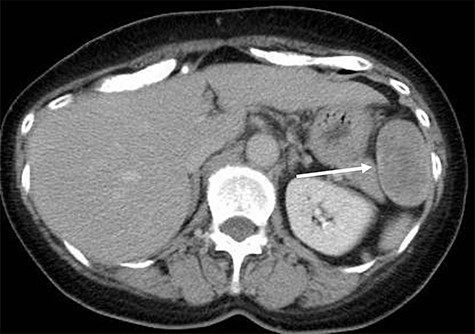

A 70-year-old woman underwent right thyroidectomy for thyroid cancer 7 years ago. An abdominal tumor was incidentally detected on computed tomography (CT) during a follow-up visit, and the patient was referred to our hospital for further evaluation. On physical examination, the mass was nonpalpable and nontender. Laboratory test results were nonspecific. Abdominal contrast-enhanced CT revealed a well-circumscribed soft tissue mass measuring 5.1 × 3.2 × 2.6 cm at the left anterolateral abdominal wall (Fig. 1). There were no signs of invasion of the adjacent organs. Magnetic resonance imaging (MRI) revealed a hypointense tumor on T1-weighted MR images with delayed enhancement in the arterial phase and a heterogeneous hyperintense tumor on T2-weighted MR images (Fig. 2a–d). The tumor was preoperatively diagnosed as a gastrointestinal tumor or a benign tumor, and it was mainly supplied by abdominal wall arteries.

Radiological findings. Computed tomography showing a well-circumscribed soft tissue mass measuring 5.1 × 3.2 × 2.6 cm in the left anterolateral abdominal wall (white arrow).